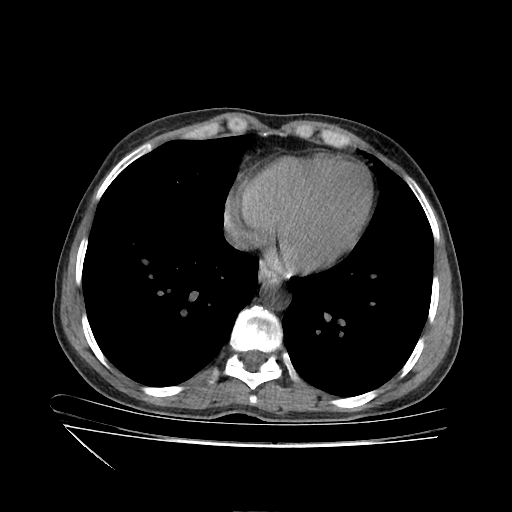

Slice 70 Targeting Evaluation

Slice: Slice_70

Conversion: NATIVE β†’ VENOUS

Original VENOUS CT scan

No window - Raw intensity values